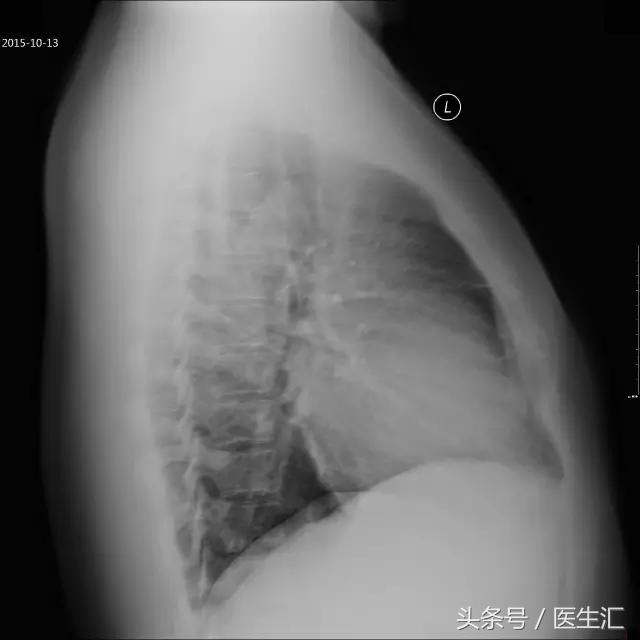

胸片

心影轻度增大(图2)(图3)(2015年10月13日)。